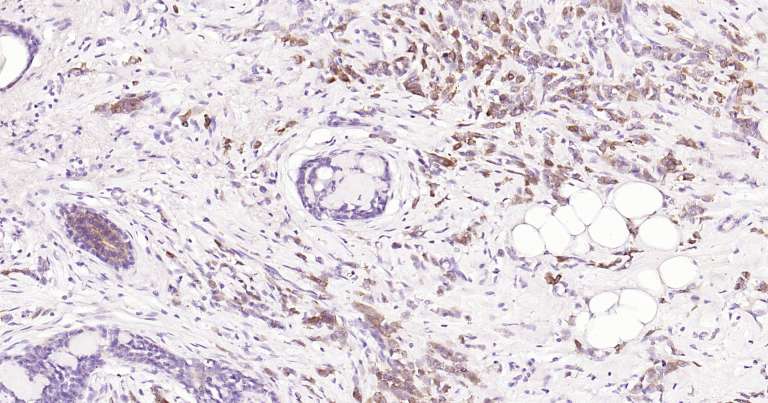

Immunohistochemical analysis of paraffin embedded human cerebellum tissue slide using IHC0175H (Human Tau-4 IHC Kit).

Immunohistochemical analysis of paraffin embedded human breast cancer tissue slide using IHC0175H (Human Tau-4 IHC Kit).

Immunohistochemical analysis of paraffin embedded human colon tissue slide using IHC0175H (Human Tau-4 IHC Kit).